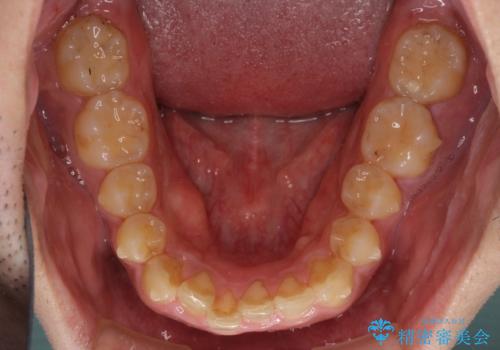

- 上下前歯のデコボコと下の前歯が隠れるほどの深い咬み合わせを気にして来院された患者様です。

インビザラインによる上下歯列の拡大と、IPR(歯と歯の間を削る)にるスペースの獲得により、口元のデコボコとディープバイトを改善することとしました。

デコボコがなくなったことで日頃の清掃が行いやすくなり、深い咬み合わせが改善したことで、食いしばりによる顎の負担も軽減されました。